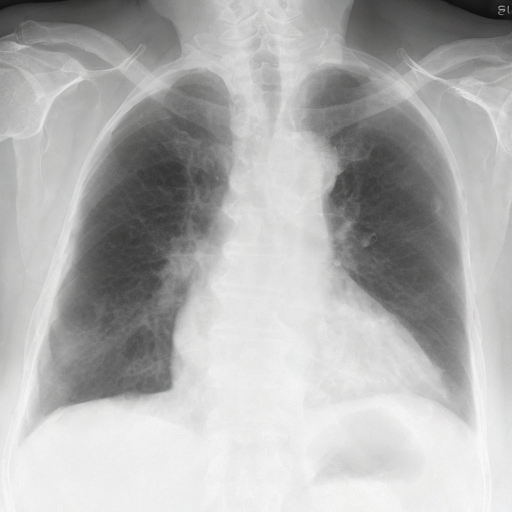

prompt = 'No acute cardiopulmonary process'

edited = radedit_pipeline(

prompt,

weights=[7.5],

image=input_image,

edit_mask=edit_mask,

keep_mask=keep_mask,

num_inference_steps=200,

invert_prompt='',

skip_ratio=0.3,

output_type="pil",

)